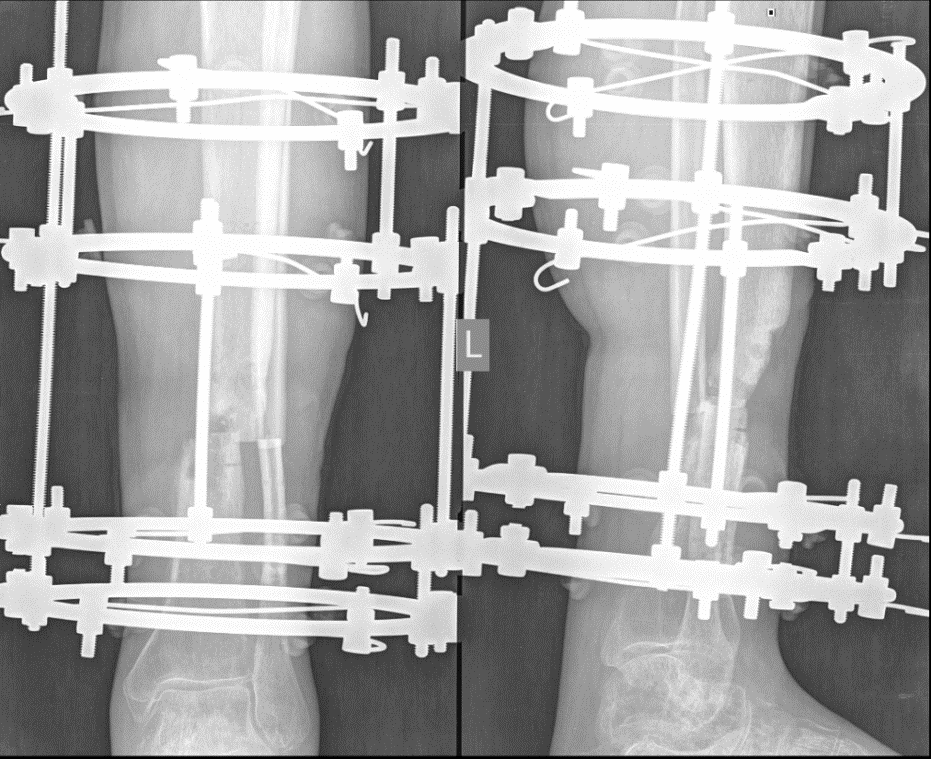

Figure 2 - Intraoperative radiograph of the left shin of patient Yu., 43 years old